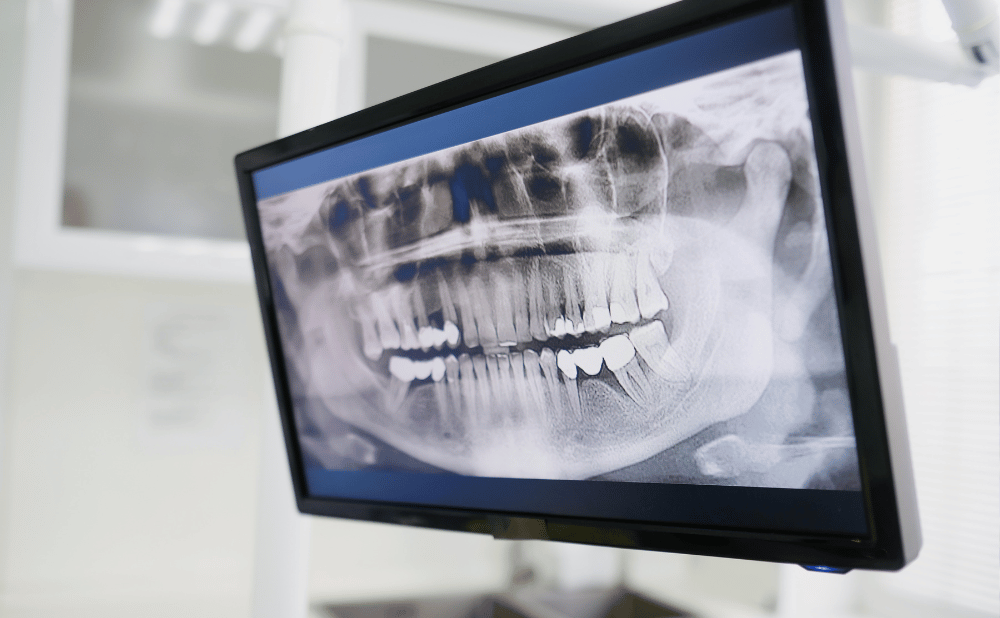

CT撮影・シミュレーション設備が整っているか

歯科用CTやシミュレーション設備が整った歯科医院では、骨の厚みや神経の位置を正確に把握できます。

これにより、難症例でも安全で正確なインプラント埋入が可能です。

歯科用CT撮影やデジタルシミュレーションによる精密検査を行うことで、以前は難しいとされたケースでも、治療可能と判断されることがあります。

当院のエックスガイドを使ったシミュレーションについては、以下のページをご参照ください。